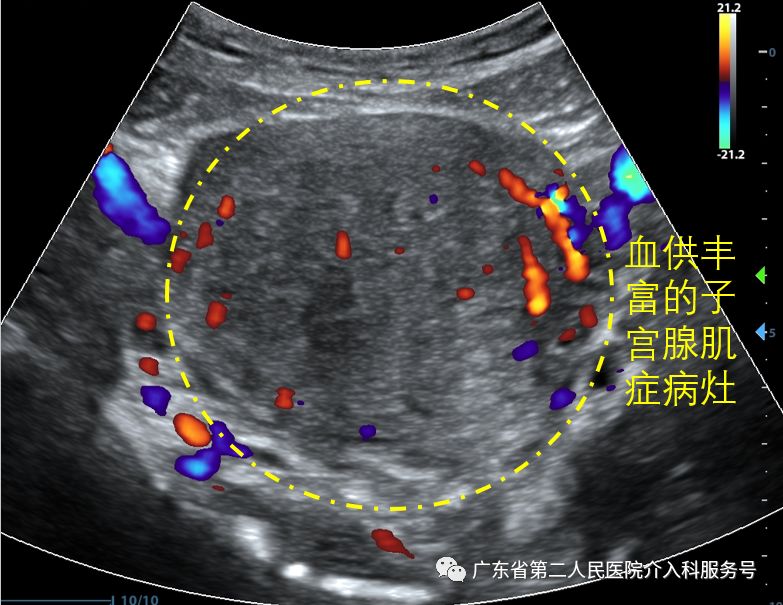

下图为消融前子宫腺肌症病灶的血供丰富。